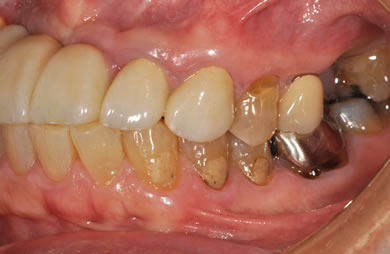

治療前

• 治療前